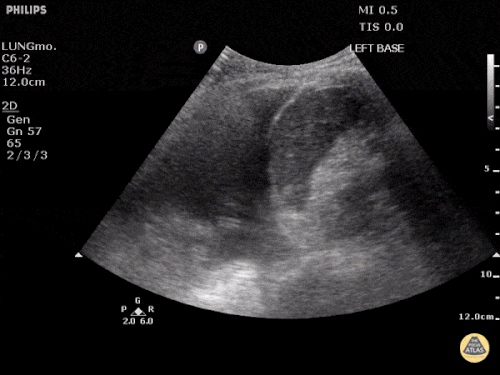

Perikarderguss/Tamponade

Der Perikarderguss, bzw. die Maximalvariante – die Tamponade – ist eine sonographisch leicht zu diagnostizierende Erkrankung, sowohl mit einem Konvex- (=Abdomen-) als auch einem Echoschallkopf. Am einfachsten gelingt der Nachweis von subxiphoidal. Der Schallkopf wird unterhalb des Xiphoids aufgesetzt und so unter die Rippen gekippt, dass das Herz zum Vorschein kommt. Hier kann man einen (relevanten) Erguss rasch erkennen. Zeichen für eine hämodynamische Relevanz sind z.B. die Kompression des rechten Vorhofs und des Ventrikels.

Quelle: http://www.thepocusatlas.com/pericardium CC BY-NC 4.0